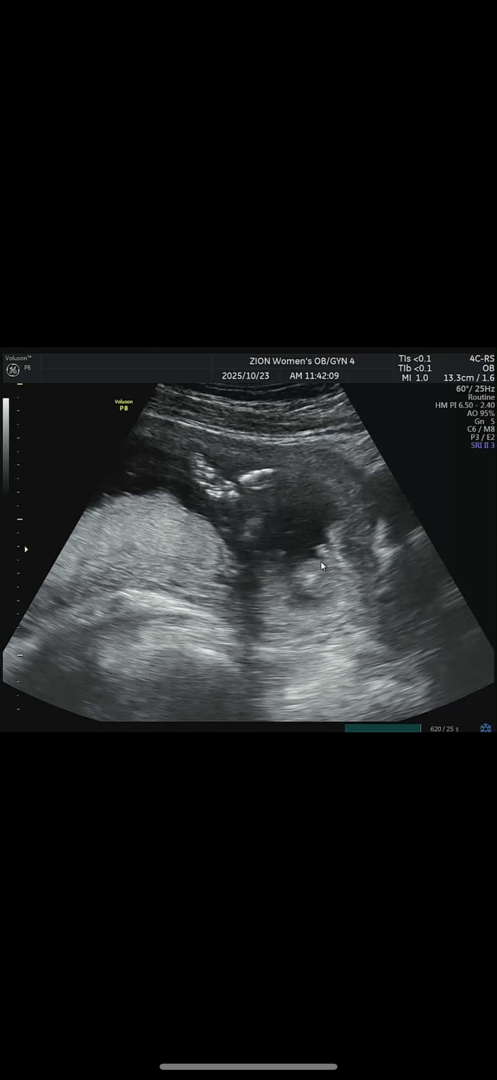

18주차인데 아직 성별이 애매하데요 ㅠㅜ 남자일까요 여자일까요

성별이 아직도 애매하네용,,,, 남자라기엔 도드라지지 않고 여자라기엔 많이 튀어나와있는데 또 이런 경우도 있다고 해서 애매하데요 ㅠㅠ 언제 알 수 있을까요,,,, 다리 사이입니장